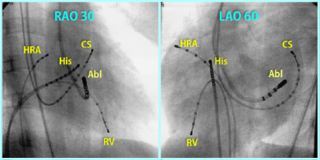

電極のついた電極カテーテルを複数用いて、これらを心臓内や心臓の周囲の静脈内などに留置し、不整脈の原因を探る検査をまず行います。電極カテーテルから心拍数130~200程度の頻拍刺激をくわえたり、わざとタイミングをずらしてペーシングをすることで、不整脈を誘発したり不整脈の素因を調べることが可能です。このような検査を電気生理検査といいます。

電気生理検査で不整脈の素因を調べた後に、アブレーション(焼灼)の標的とすべき部位を決定し、さらにアブレーションカテーテルの先端の電極で心内心電図を観察しながら操作して至適部位を再確認していきます。標的部位が決まればそこにカテーテル先端をおき、高周波通電をおこないます。カテーテル先端温度を50℃~60℃程度に制御しながら高周波通電をすると、カテーテル先端付近の約半径5mm程度の心筋が加熱されて変性します。不整脈を根絶するまでこのように高周波通電を数回から十数回繰り返します。